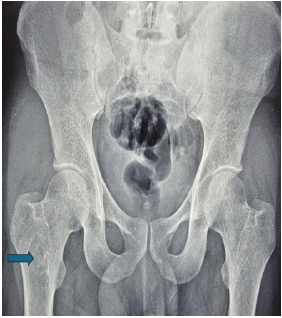

Disseminated Skeletal Cryptococcosis: A Case Report

David Joseph , Prannoy Paul , Vishnu Padmanabhan , Athul Rajesh , Raj Vignesh , Raphael Baby

………………………………p.130-134